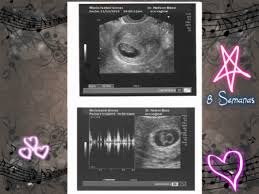

Semana 8 De Embarazo Ya Puedes Escuchar El Latido De Su Corazon